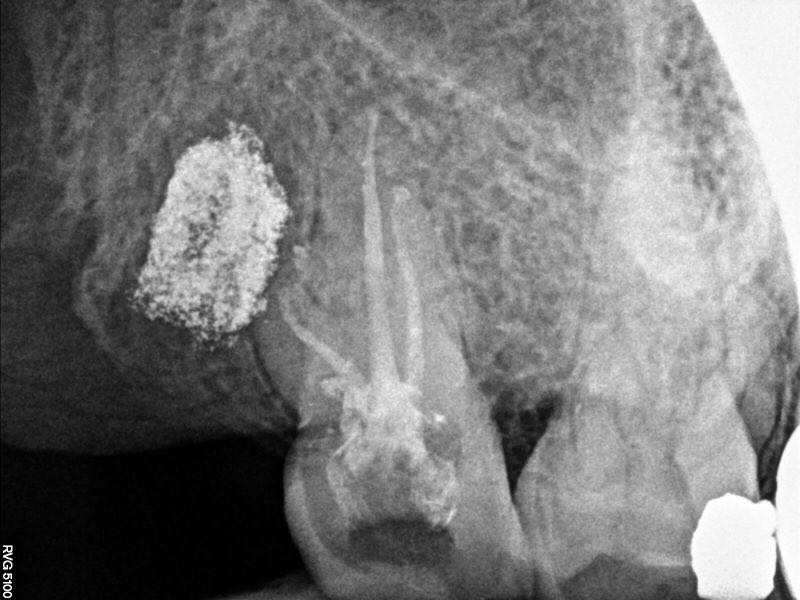

根充片

面对重度弯曲的根管,手用器械有时根本下不去,本病例运用手用锉疏通至10#换pathfile锉,之后用PROTAPER NEXT备根管,镍钛器械最大的优势就是能尽量保证根管形态,不易将弯根拉直及形成台阶,提高工作效率